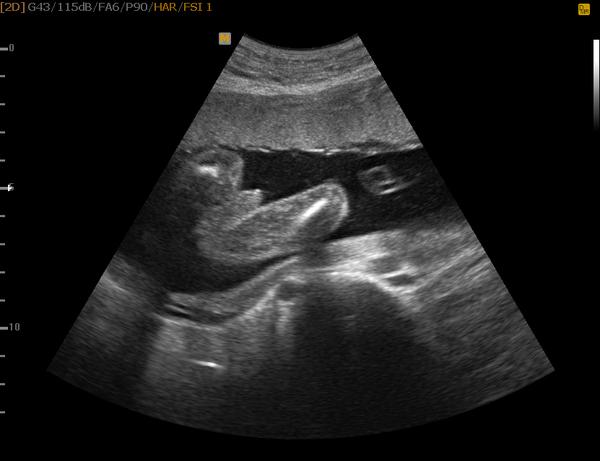

@teere kluk jak buk takovy utz jsem uz mela nekolikrat tam je krasne videt pytlik

Kluuuk 🙂